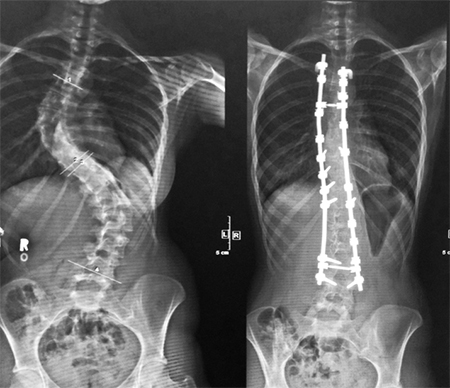

Before and after radiograph of a patient with scoliosis following traditional spinal fusion surgery.

Patients with curves over 50° are considered for surgery. Spinal fusion surgery has undergone numerous changes since its inception. Traditional surgery can last upwards of ten hours and recovery takes around two months. This can severely interrupt the active lives of young patients. In recent years, the scoliosis community has witnessed an increase in the variety of surgical methods available, most notably Vertebral Body Tethering and Apifix (Israel). I understand that these new surgical interventions shorten recovery time and permit mobility.